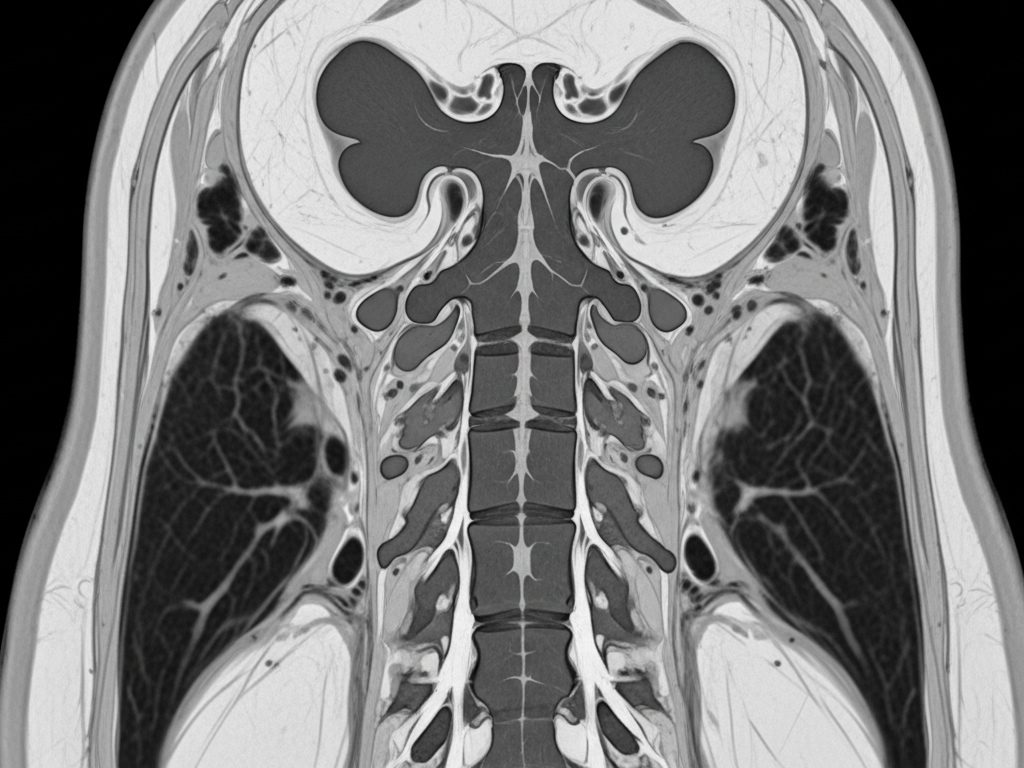

Actualmente, para conocer si una persona tiene un problema en la médula espinal, las alternativas son la radiología, la tomografía computada y la resonancia magnética, las que sólo entregan información de alteraciones estructurales, pero no funcionales, de la médula espinal.

- Permite evaluar la función de la médula espinal, a diferencia de la tomografía computarizada y la resonancia magnética que solo aportan información estructural de la médula espinal.